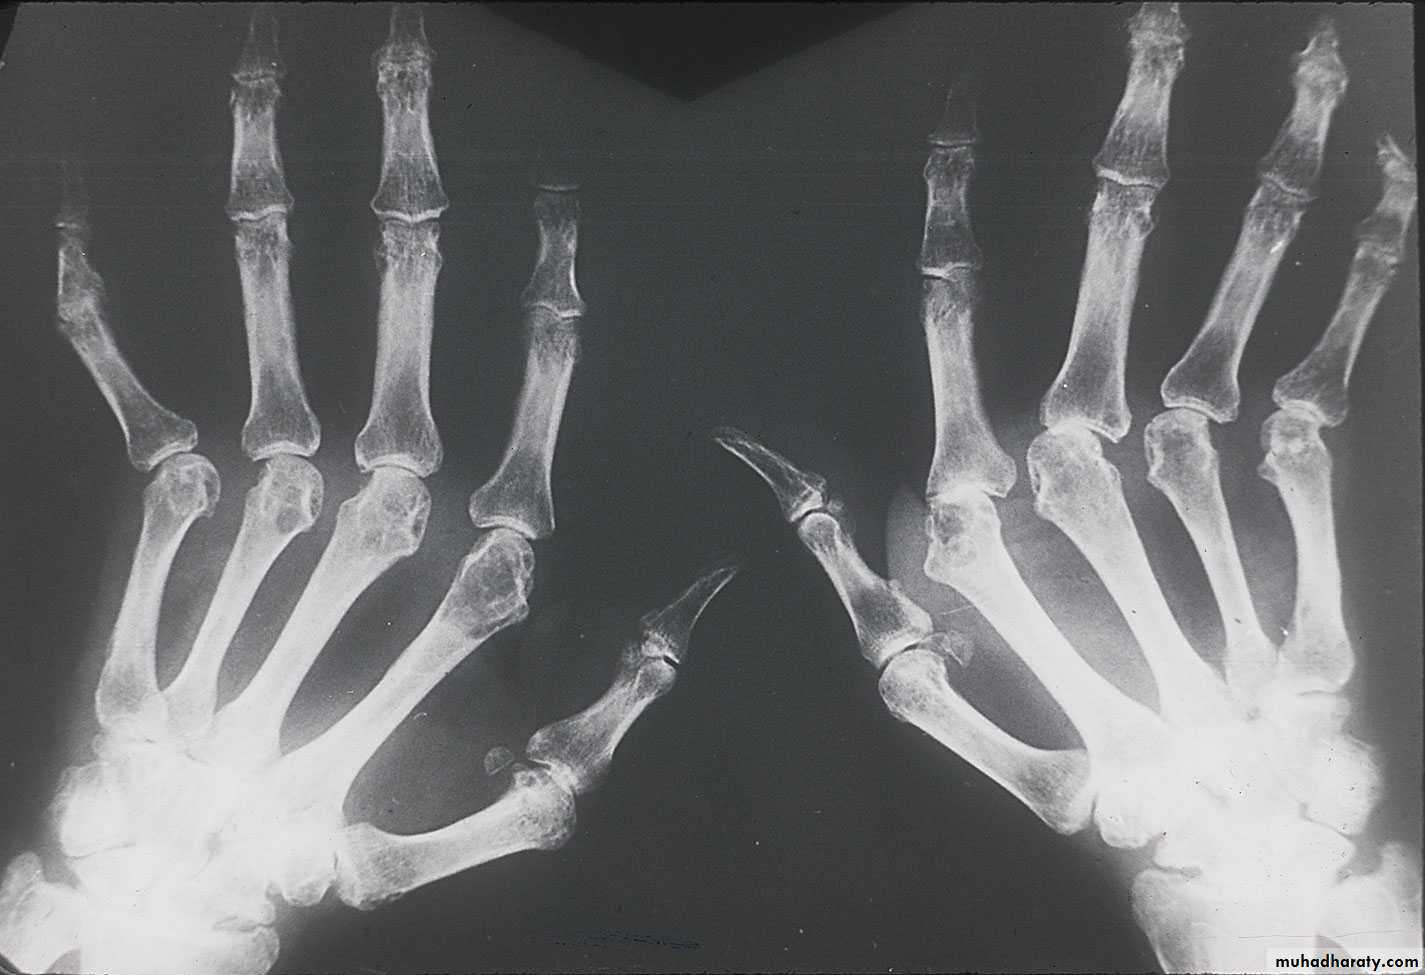

Provide a good reflection of disease activity. The typical features are symmetrical swelling of MCP& PIP joints. They are hot, tender & have stress pain on passive movement.

Specific hand abnormalities include swan neck deformity, button hole (boutonnière) deformity& Z- deformity of thumb. Other abnormalities include :

dorsal subluxation of ulnar styloid of the wrist , trigger finger, cock up deformity of the toe, flatfoot, Baker's(popliteal) cyst which can be mistaken for DVT, but past history of joint disease & Doppler U/S can establish the diagnosis of DVT.

3- X-ray: the typical radiographic changes of RA are periarticular osteopenia& marginal non proliferative erosions.